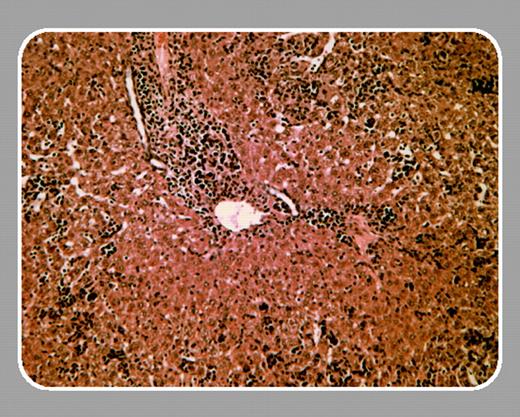

Fascinating insight into the role of phospolipid phosphatases in hematopoiesis has been gained by analyzing knockout mice. Targeted disruption of SHIP results in a myeloproliferative syndrome characterized by splenomegaly and extramedullary hematopoiesis.3 Granulocyte-macrophage progenitor cells are expanded and hypersensitive to growth factors. Pten-/- mice are embryonic lethal. Heterozygous Pten+/- mice survive but frequently develop cancer of different organs, consistent with the known function of Pten as a tumor suppressor.4 The hematopoietic phenotype of these mice is characterized by a progressive lymphoproliferative disease. In this issue of Blood, Moody and colleagues (page 4503) describe the complex hematopoietic phenotype of Pten+/- SHIP-/- mice. The aim of combining haploinsufficiency for Pten with SHIP deficiency was to exaggerate PIP3 dysregulation, potentially leading to leukemogenesis. Surprisingly, Pten+/- SHIP-/- mice did not develop myeloproliferation but did develop a myelodysplasia-like syndrome, characterized by marked leukocytosis, anemia, and thrombocytopenia that was not observed in SHIP knockout mice. Correspondingly, erythroid, megakaryocytic, and primitive myeloid (GEMM) progenitor numbers in bone marrow were markedly reduced. In some aspects, Pten heterozygosity did further aggravate the SHIP-/- phenotype: Pten+/- SHIP-/- hematopoietic progenitors were hyperresponsive to growth factors, and Pten+/- SHIP-/- mice demonstrated an even more pronounced extramedullary hematopoiesis compared with SHIP knockout mice. Interestingly, however, leukemic transformation could not be observed during the limited lifespan of the mice.FIG1